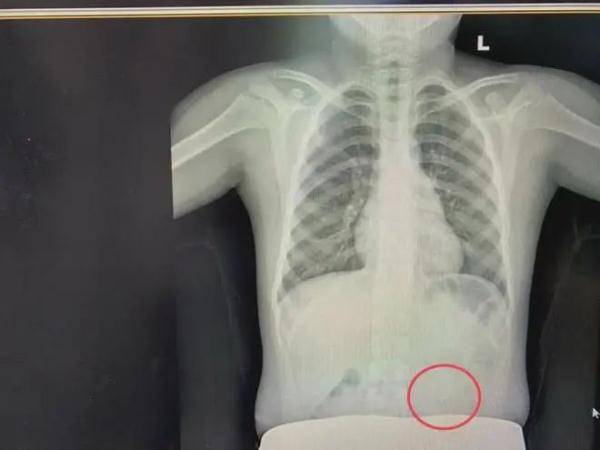

医生为其安排了急诊胃镜检查

发现金属丝对折后长约5-6厘米

已滑入胃腔内

所幸最终被成功取出

考虑到铁丝很有可能划破腹部内部器官和肠道,医护人员迅速为孩子进行了CT检查。发现铁丝团直径长约1厘米多,因为患者喝过水加速了肠胃蠕动,腹部铁丝团已经从胃部转移到肠道。